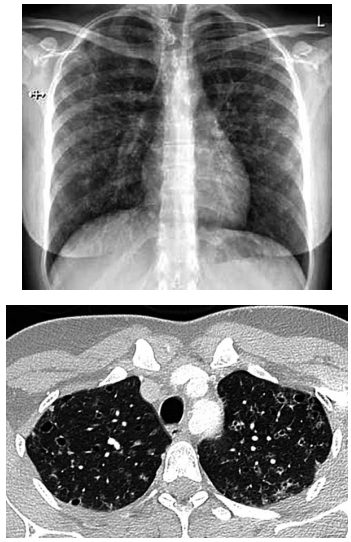

Mulher de 26 anos tem história de tosse crônica com secreção amarelada associada a dispneia ao subir escadas rapidamente. Ela fuma trinta cigarros por dia, com histórico de 13 anos-maço. Os testes de função pulmonar revelam (% do previsto): VEF1: 94%; capacidade vital forçada: 94%; capacidade pulmonar total: 107%; capacidade pulmonar de difusão de monóxido de carbono (TLCO): 57%. A radiografia e tomografia realizadas são mostradas a seguir: